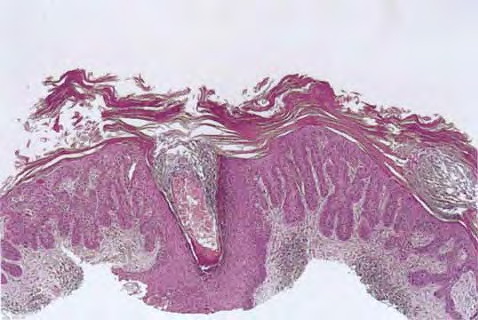

Hypertrophic actinic keratosis = التقران الضيائي الضخامي